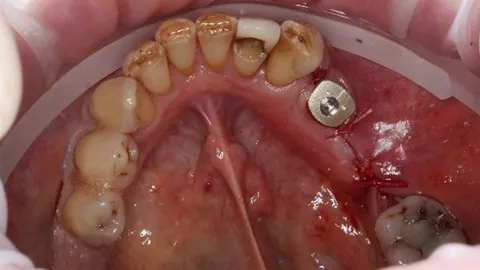

Suturing was adapted to each implant site. The distal implant was fully submerged with a cover screw, requiring complete primary closure. At the mesial implant, where a HealFit® SH abutment was placed, only two simple interrupted sutures were placed mesially and distally to stabilize the soft tissues.

8. Suturing was adapted to each implant site. The distal implant was fully submerged with a cover screw, requiring complete primary closure. At the mesial implant, where a HealFit® SH abutment was placed, only two simple interrupted sutures were placed mesially and distally to stabilize the soft tissues.

Three months after implant placement, a second‑stage surgery was performed at the distal site to uncover the implant following successful osseointegration. A standard healing abutment was placed, as this implant had initially been placed subcrestally with a cover screw due to insufficient primary stability and required conventional freehand placement.

In contrast, the mesial implant had achieved adequate primary stability at surgery, allowing the use of a HealFit® SH anatomical healing abutment from the time of placement. This resulted in progressive transmucosal shaping without the need for additional surgical intervention. At re‑evaluation (8.), peri‑implant soft‑tissue maturation was already complete at this site, illustrating the clinical advantages of immediate transmucosal conditioning, including reduced need for second‑stage surgery, minimised soft‑tissue trauma, improved emergence profile development, and a more streamlined prosthetic workflow.